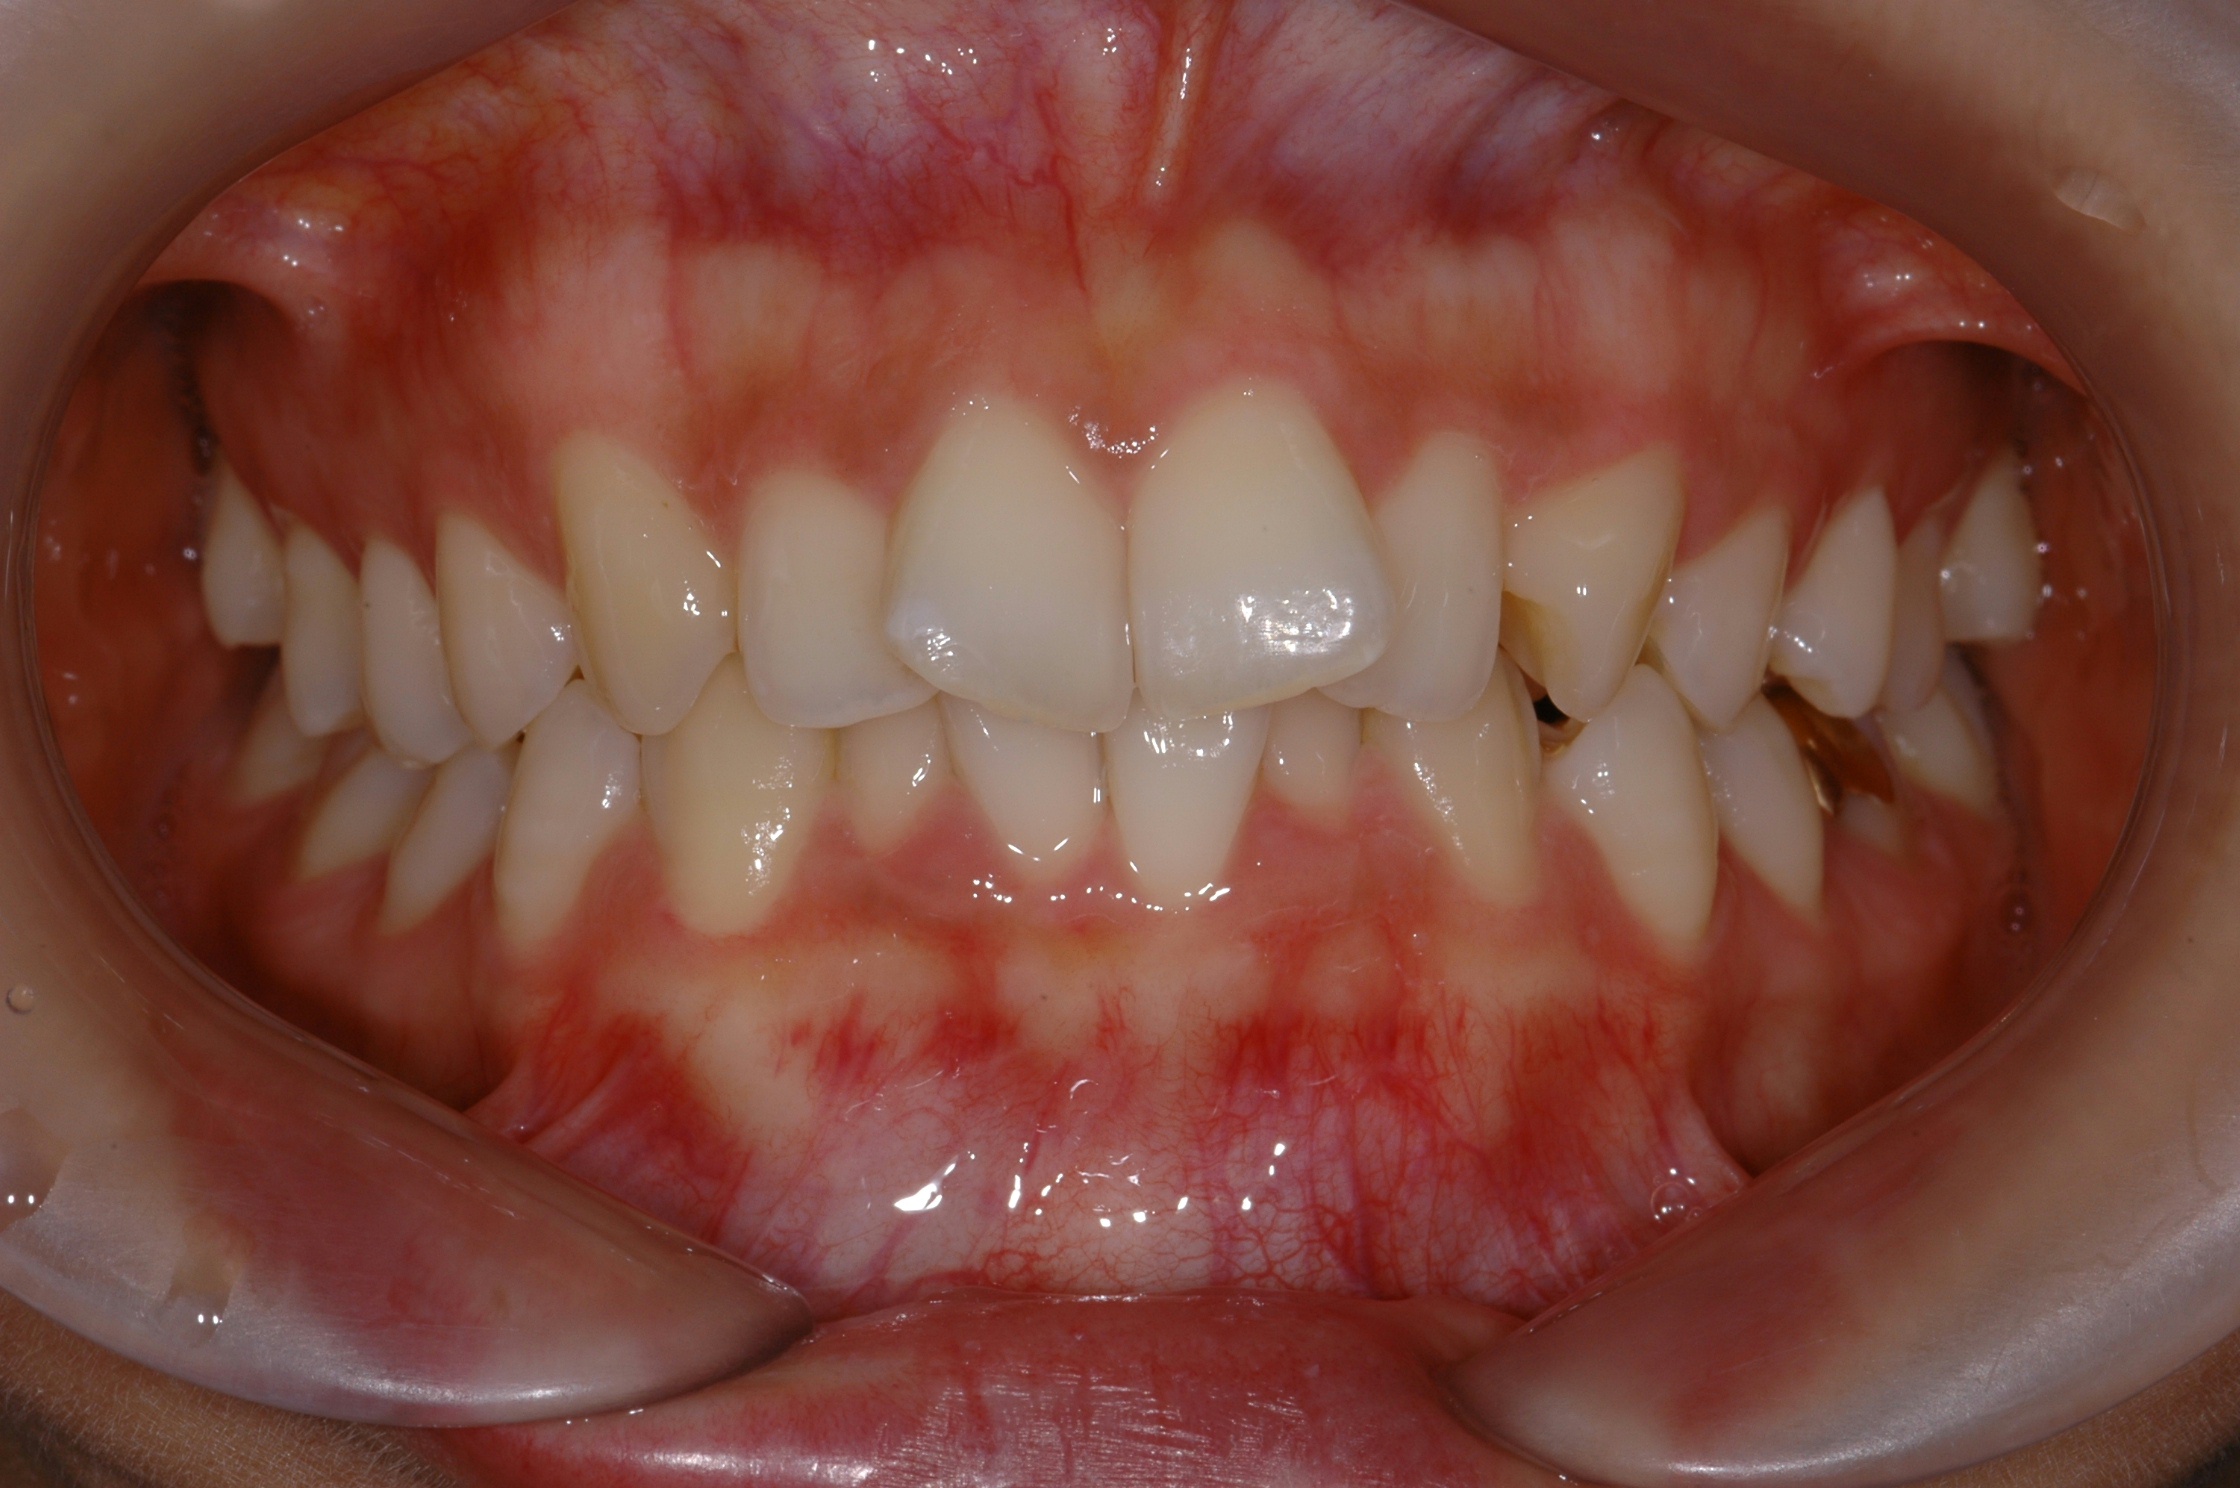

치료 후 사진입니다.